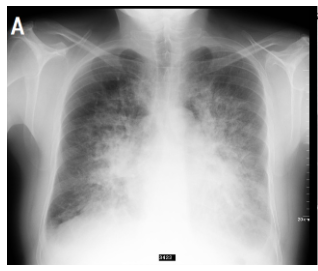

Pulmonary oedema is a condition where fluid builds up in the alveoli of the lungs, displacing air and reducing the amount of oxygen available.

Pulmonary oedema is defined as an abnormal accumulation of extravascular fluid in the lung parenchyma and disrupt normal gas exchange.